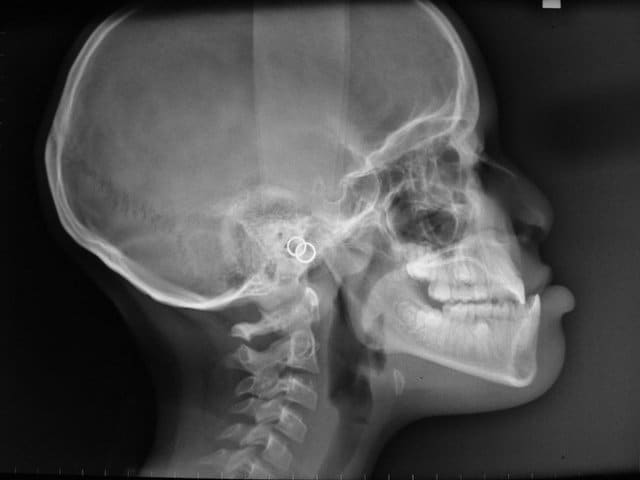

07/05/2009 à 15h56

ci joint la télé, pour les photo il va falloir attendre le prochain rdv